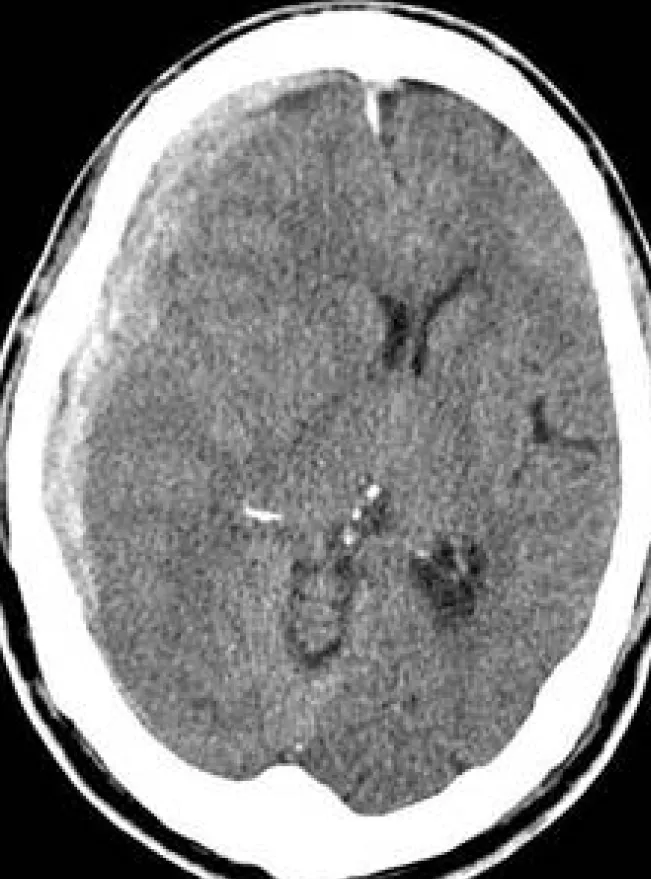

詳解

破題關鍵

這題的解題核心是判讀腦部電腦斷層影像,辨識出硬腦膜下出血的典型影像特徵。圖片中大範圍、呈半月形(crescent shape)的高密度病灶,緊貼顱骨內緣,是診斷硬腦膜下出血最關鍵的視覺線索。

選項拆解

登入查看完整詳解與互動作答